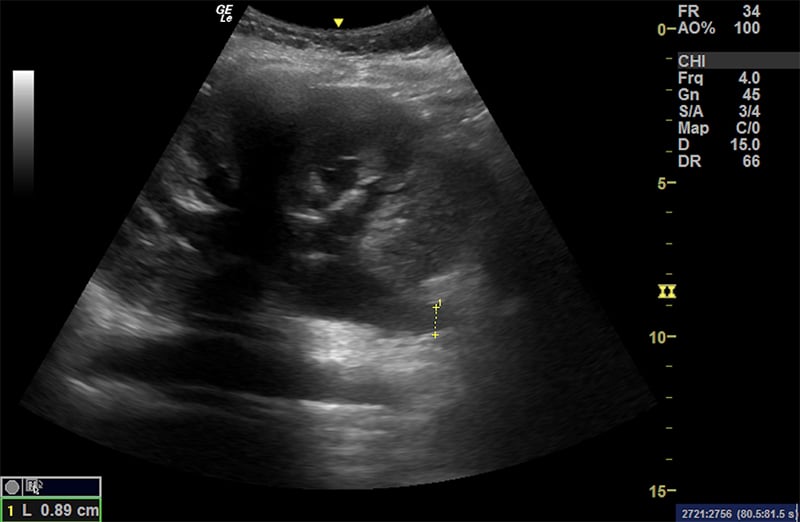

- Greatest Vertical Pocket (GVP).

- After scanning the entire uterine cavity systematically (mowing the lawn), find and measure the single deepest pocket of anechoic amniotic fluid perpendicular to the bed with no fetal parts present. The probe marker should be pointing to the patient’s head.

- Normal ranges from 2cm – 8cm

Figure 37. A normal greatest vertical pocket of amniotic fluid. Note the calipers measuring the deepest pocket of amniotic fluid not containing any fetal parts.